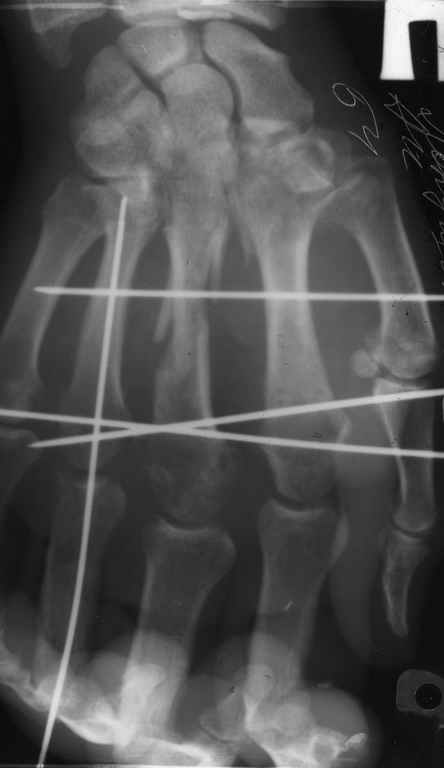

Диагноз: Стойкая Смешанная дермотеногенная контрактура 3,4 пальца правой кисти.

Запрос: дальнейшая тактика лечения.

Судя по выписному эпикризу, рентгенограммам и фотографиям, пациенту

показано этапное лечение.

К сожалению, мне непонятна локализация кадра

(прилагаю).

Это 3 или 4 межпальцевой промежуток? Гранулирующая рана или свищ?